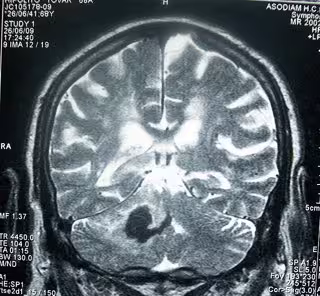

Cerebro

BOBJGALINDO/WIKIMEDIA COMMONS